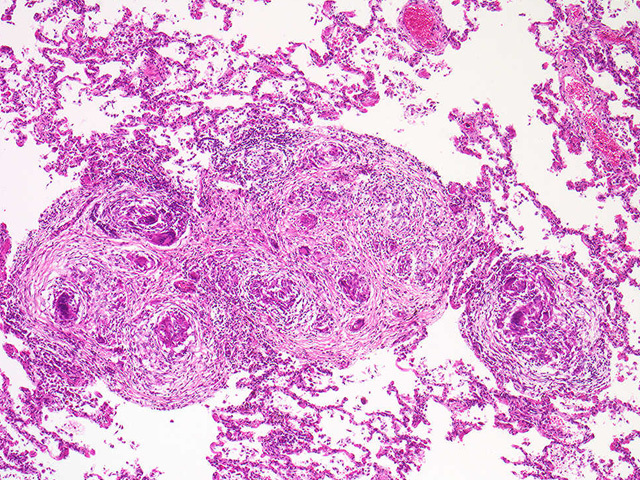

Lung biopsy was taken from an AAF complaining of joint pain. CXR showed hilar adenopathy. What is condition?

Describe histo

Sarcoidosis

Central of non-caseating granuloma: epitheloid macrophages surrounded by rim of mononuclear cells. Multinucleated giant cells also seen at higher mag.

Accumulation of CD4+ Tcells a cause